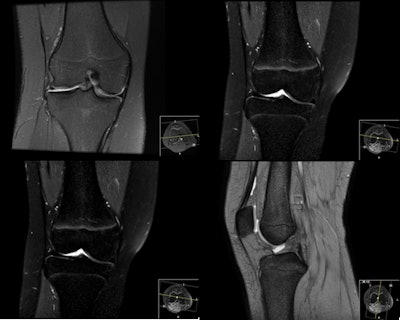

Part of the appeal of MRI in young footballers is its lack of ionizing radiation, and the modality has been used in wrist assessments by the International Federation of Association Football (FIFA) since 2003.

MRI is not currently used to assess bone age in routine practice, but Diaz believes that it could be standardized to become an option both in clinical diagnosis of special syndromes and in forensic work, the latter being the main focus of her presentation today. As an adjunct to other methods, MRI yields accurate results to specific questions, but there are pitfalls, and problems can arise from the absence of standards to ensure that the age established by the scientific evidence is correct. Moreover, the fact that research predominantly pertains to males and Caucasians means that it cannot be used as a general reference.

"There are not enough studies that represent the entire population. Instead small studies aim to answer specific questions," she told ECR Today. "Furthermore, some involve several grade scales of the same body part examined with different MR field strengths. The interpretation of these grade scales may be confusing to inexperienced radiologists."

She pointed to other studies which found that because MRI is a lengthy process and sensitive to body movement, this is a significant limitation of its use children.

Other factors in bone age estimation remain controversial: gender, ethnicity, nutrition, physical activity, geographical location, other socioeconomic factors, and exposure to the sun as an acceleration factor in maturation should all be considered. Widening study cohorts to include a range of different groups of subjects could also be looked at and would constitute a way of reaching consensus on protocols and grade scales. These studies must be wide, multicenter and guarantee the inclusion of these different factors, according to Diaz.